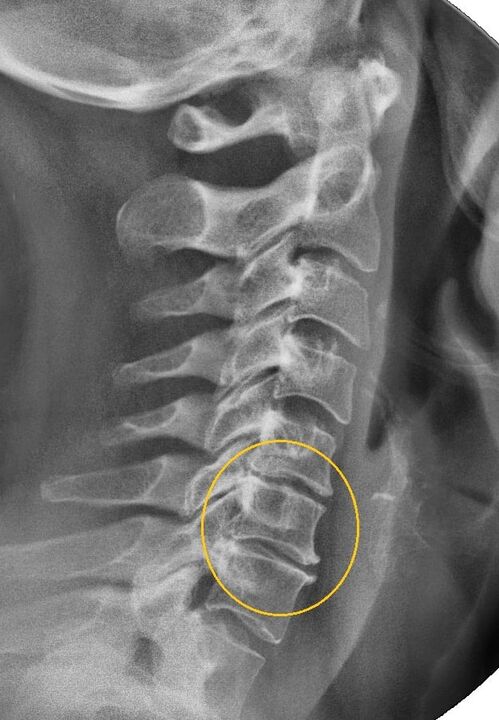

O procedimento diagnóstico mais informativo é a radiografia. As patologias de 1º grau correspondem ao 1º ou 2º estágio radiológico. As imagens resultantes visualizam sinais típicos da doença.

| Estágios radiográficos da osteocondrose cervical de 1º grau | Sinais característicos |

|---|---|

| Estágio 1 | Pequenas alterações na curvatura da coluna vertebral na região cervical, afetando um ou mais segmentos |

| Estágio 2 | Ligeiro espessamento dos discos intervertebrais, deformação dos processos uncinados, endireitamento da lordose, pequenos crescimentos das estruturas ósseas |